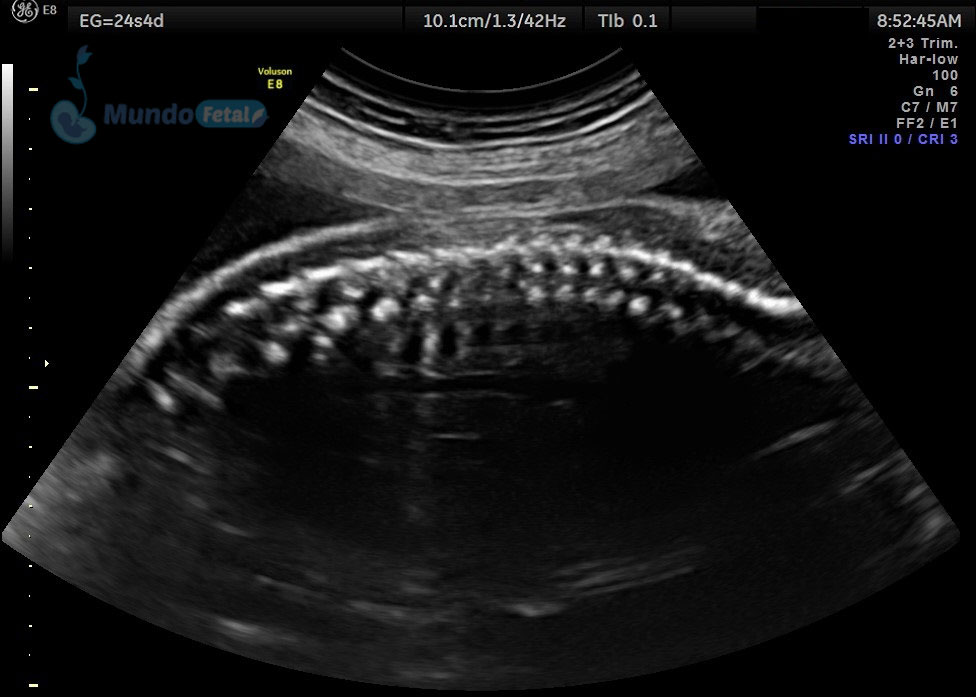

Entre las 18 y 22 semanas, el feto ha desarrollado la mayoría de sus estructuras anatómicas, permitiéndonos valorar de manera detallada todos los órganos del bebe, descartando anomalías anatómicas fetales y datos de cromosomopatías. Prediciendo además preeclampsia (Doppler de arterias uterinas) y parto prematuro (por medio de la medición de la longitud del cérvix). En manos expertas, la detección de anomalías anatómicas supera el 80%.

Ultrasonido 2do Trimestre 18-23 Semanas (Estructural o Anatómico)